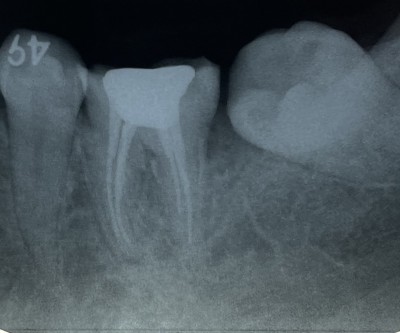

【下顎第二大臼歯】根管治療2年経過

2023.06.18 症例紹介